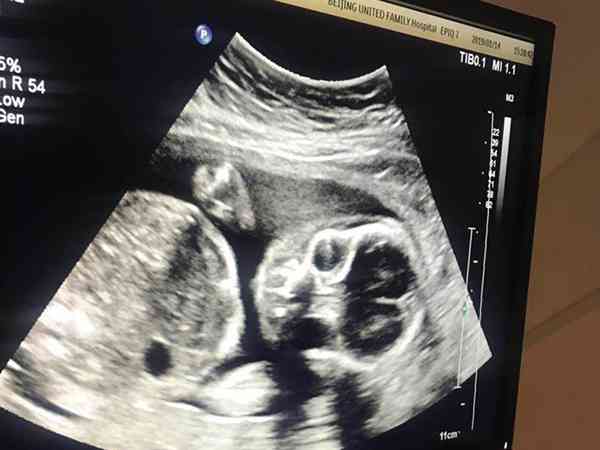

怀孕后在不知道的情况下,有喝酒,而且还吃了不少次布洛芬,知道怀孕后有积极做检查,目前看来宝宝情况都是正常的,也没有出现先兆流产,医生让我在孕后期做好排畸检查就可以了。再过段时间就需要做nt检查了,但医生更建议我去做无创dna。我想知道无创DNA产前检测和nt检查的区别在哪里呢?哪一个准确率更高?孕后喝酒、吃布洛芬,建议无创dna检和nt检查都做。因为nt检查主要是看小孩颈后透明带的厚度,这是每一个孕妇都要做的。nt检查是最早的排畸超声。它跟染色体筛查是两回事情,所以说nt检查是一定要做的。至于无创dna还是唐氏筛查,只用选择其中一种就可以。

无创dna能筛查21、18、13三体。其中21三体准确率能达到99%。但是唐氏筛查,是化学的方法,它主要通过人体的一些指标监测来判断染色体异常的概率,它的准确率只有70~80%。但它擅长的面会比较广,只要有染色体异常,导致人体内化学指标的变化及有可能被筛查到。所以如果说你想做的更全面的染色体筛查,可以考虑无创和唐氏筛查一起都做了。如果没有这方面需求的话,直接做唐氏筛查或者无创dna都可以。

孩子出现胎停育有百分之五六十的原因是因为染色体异常导致的,而染色体异常比较严重的孩子会直接在早期出现胎停育,还有一部分不太严重的孩子会活到中孕期,甚至会正常出生,在出生之后才被发现,这种情况是存在的。所以说孕期做好排畸超声,染色体筛查很重要,就目前你这种情况流产的可能性不大,可以不用太担心。